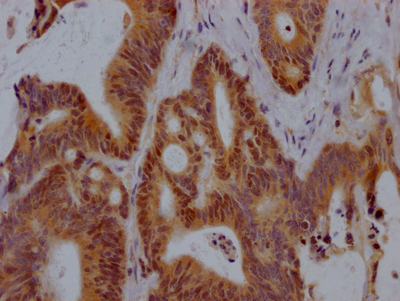

圖片:

應用范圍:ELISA, IF

Application Recommended Dilution IF 1:50-1:200 -